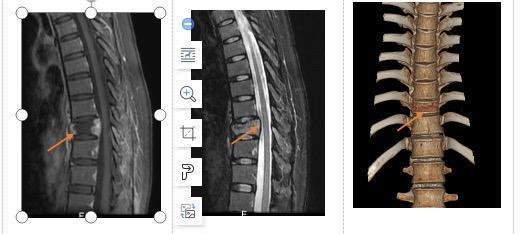

经过院方严谨的讨论后决定实施代表脊柱肿瘤领域最高水平的手术——胸10椎肿瘤完整切除(En-bloc切除)+3D打印人工椎体置换术。

全脊椎整块切除术一度被认为是脊柱手术的禁区,该类手术操作难度高,出血多,风险非常大,对医生手术技术要求非常高,是公认的脊柱肿瘤领域的高难度手术。为此,团队决定使用3D打印人工椎体结合椎弓根钉棒系统来解决脊柱稳定的问题。

对于复杂的脊柱畸形、肿瘤等病例,3D打印病变模型为手术医生策划手术提供了形象生动的参照物。定制式置入假体的应用,以“量体定制”的假体进行有效填充及修复,可以根据病变解剖部位特点设计与之高度适配的内固定装置,达到术后脊柱结构的即刻稳定。